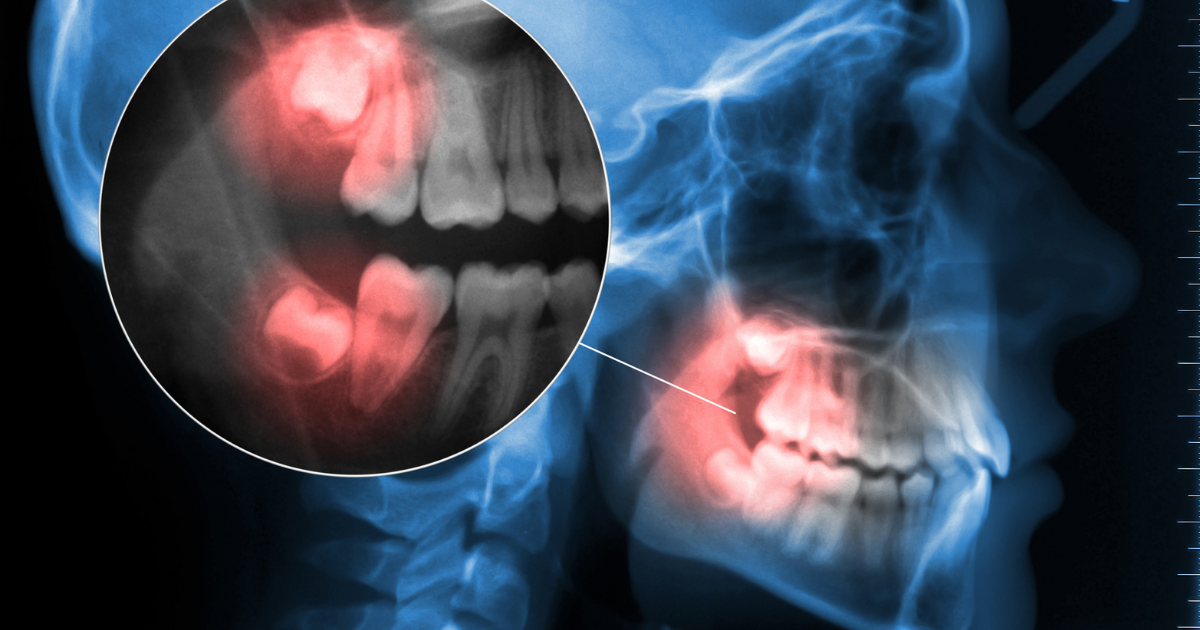

Impacted wisdom teeth are usually a result of trauma experienced by the tooth while it is developing in the jawbone. It can cause pain, swelling, and bleeding when brushing or flossing your teeth. However, most impacted wisdom teeth aren't visible without an x-ray and often don't require any treatment until they become inflamed or infected.

The dentist will need to look at your teeth and mouth to diagnose this condition. They'll likely use x-rays or an endoscope if they think something is wrong with one of your impacted wisdom teeth.

A dental exam diagnoses an impacted wisdom tooth. The dentist will ask you about your symptoms, general health, and dental x-rays to determine the severity of an impacting tooth.

If not treated quickly enough, the examination can show signs of infection or bone loss damage.